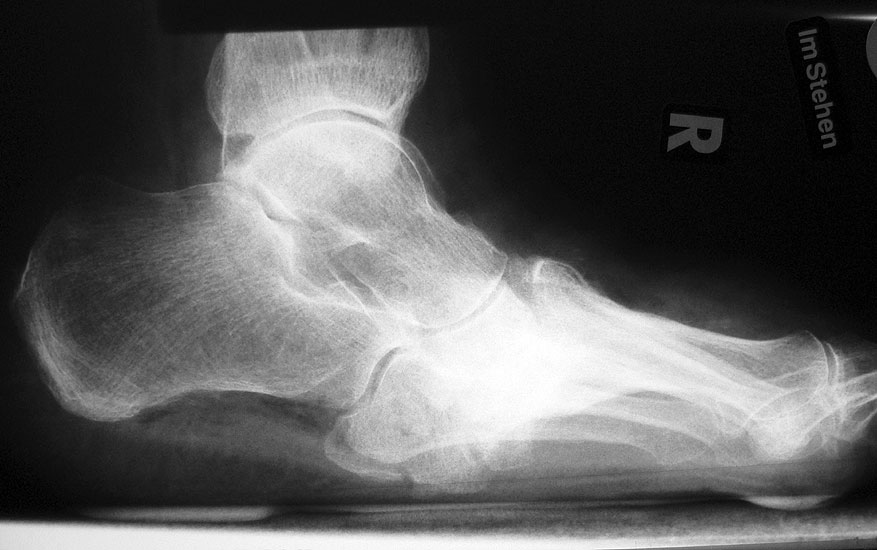

Abbildung 2

DNOAP Typ I (Abb. 2):

Hierbei handelt es sich um Nekrosen der Interphalangeal-, Metatatarsophalangealgelenke und Metatarsalia, was es zur knöchernen Resorption an den Mittelfußköpfchen und Zehengliedern führt. Die Stummel der Metatarsalia gleichen abgelutschten Zuckerstengeln, bohren sich in der Abstoßphase in die Sohle und führen zum Malum perforans.